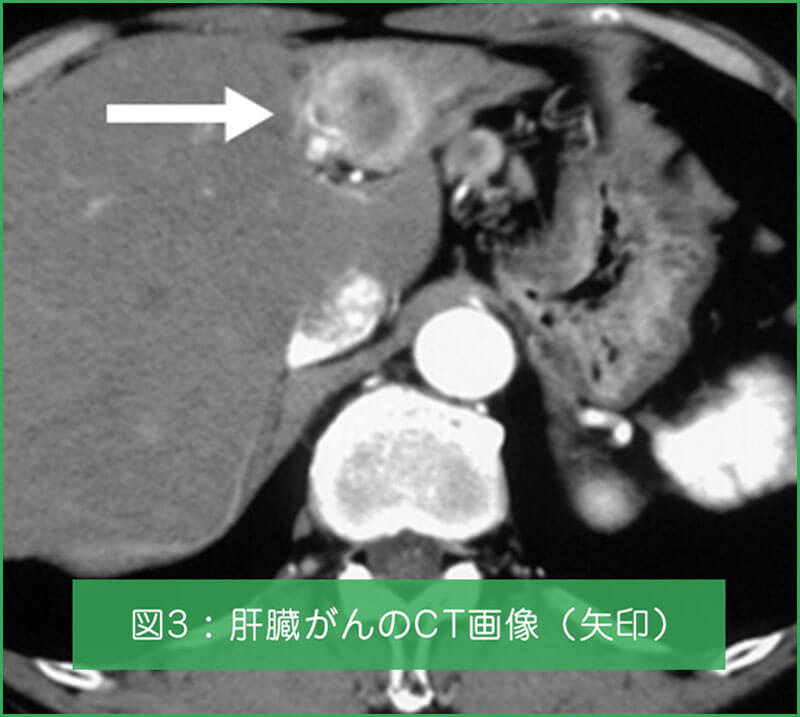

図1は慢性肝炎・肝硬変の腹腔鏡画像です。慢性肝炎はおもにB型肝炎ウィルス、C型肝炎ウィルスを原因として起こる肝臓の病気です。肝炎が進行すると肝硬変となり、食道静脈瘤(図2)や肝がん(図3)などの重大な合併症を引き起こします。